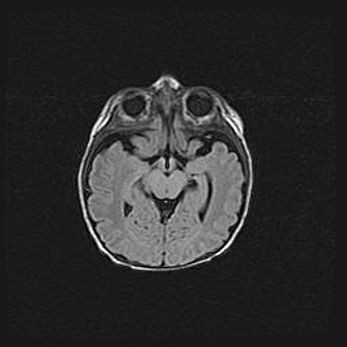

Мальформация Денди-Уокера. Киста задней черепной ямки.

Агенезия мозолистого тела.

Возраст: 2,5 месяца

Вес: 2420 г

Пол: женский

Окружность головы: 37 см

Срок гестации: 32 недели

Мальформация Денди—Уокера — редкий вид патологии ЦНС, представляющий собой врожденный порок развития каудального отдела ствола и червя мозжечка, ведущий к неполному раскрытию срединной (Мажанди) и латеральных (Лушка) апертур IV желудочка мозга. Для этогно синдрома характерна триада симптомов: гипотрофия червя мозжечка и/или полушарий мозжечка, кисты задней черепной ямки, гидроцефалия различной степени. В 70% случаев порок сочетается и с другими аномалиями головного мозга, в частности с агенезией мозолистого тела.